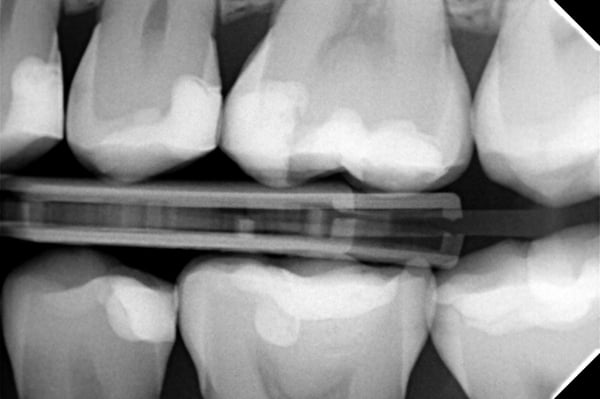

Nach dem Polieren wurde die Füllung mit einem Oberflächenversiegler (PermaSeal™ Kompositsversiegler, Ultradent Products) beschichtet. Danach erfolgte die abschließende Kontrolle mittels Okklusalprüfung und Röntgenaufnahme.

Auf den finalen Fotos wird deutlich, dass Transcend Universalkomposit der Restauration ein außergewöhnlich ästhetisches Erscheinungsbild verleiht. Das Halo Teilmatrizensystem ermöglichte zudem die Herstellung einer hervorragenden approximalen Anatomie, wie die Röntgenaufnahme belegt.